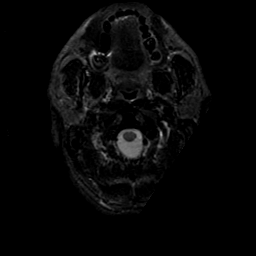

MR Study #21, November 3, 1991 -- Slice #0

[Home][Help][Clinical][Tour 1][Tour 2] Slice 0